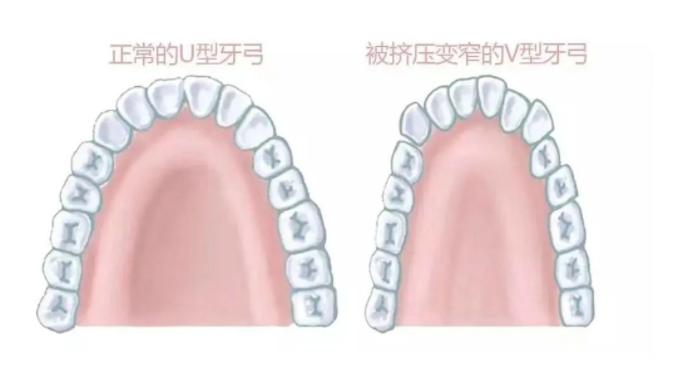

因为口呼吸的时候,下巴会后旋,外界的气压会压迫我们的颊肌,然后颊肌会压迫牙弓,让上牙弓变得特别狭窄,并且突出去,上颚特别高拱,龅牙就会越来越明显。